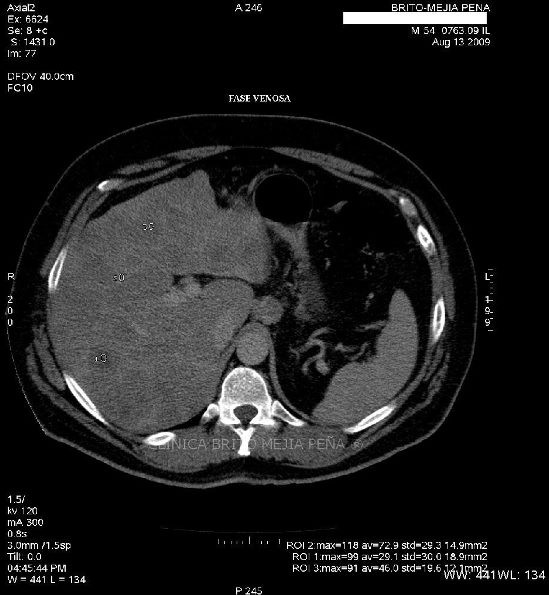

Metástasis hígado fase venosa